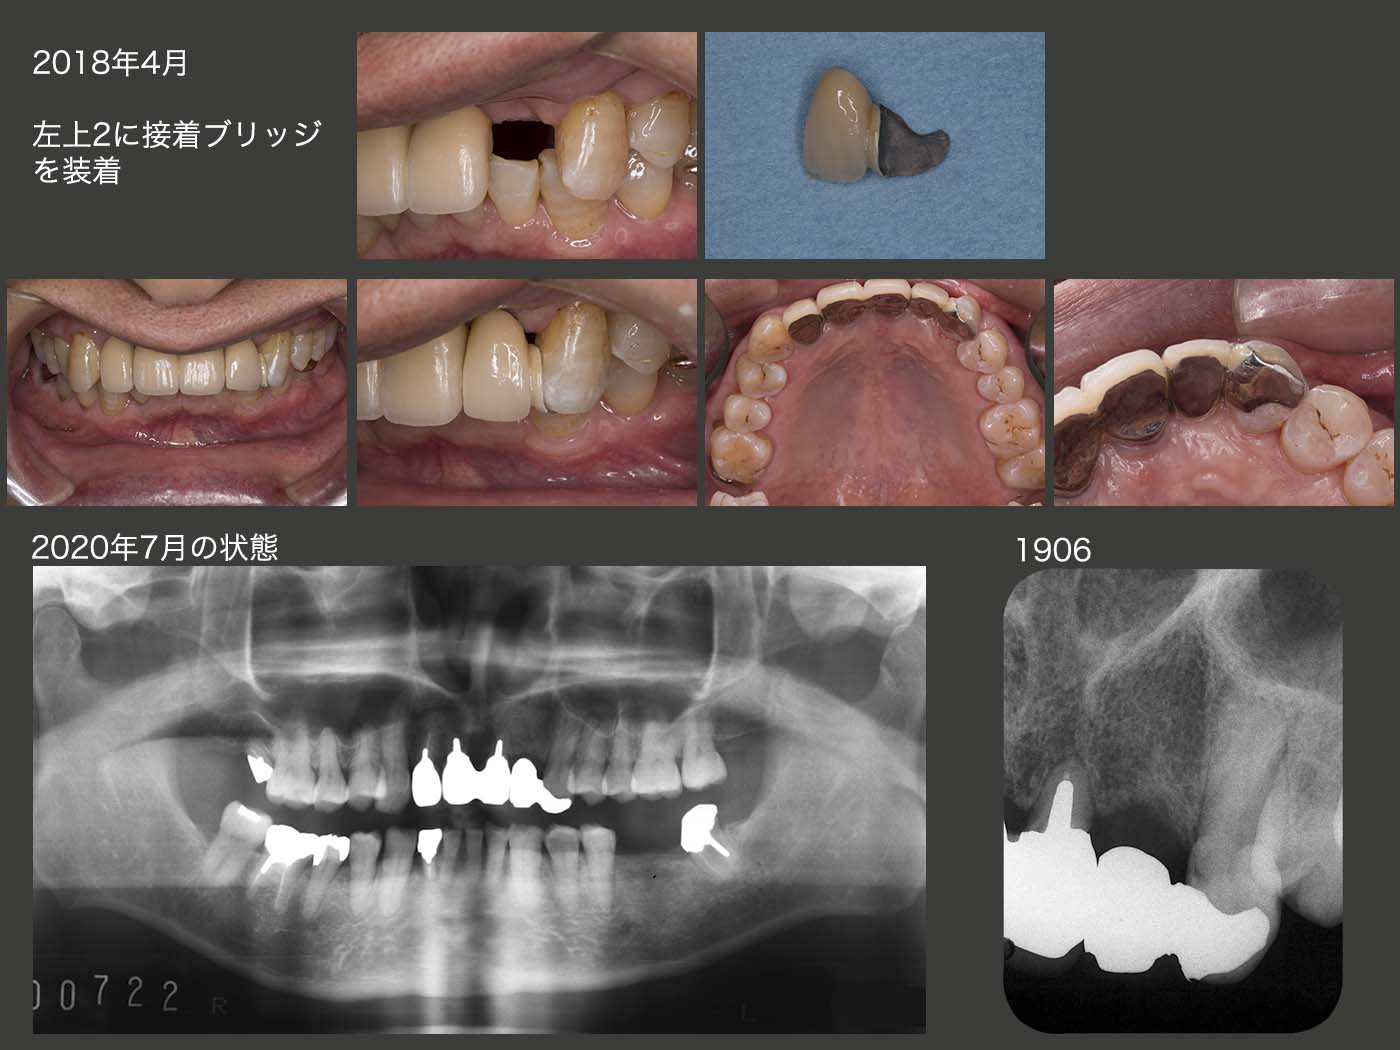

しかし,悲しいことに18年1月,今度はお握りを食べて脱落してしまった.患者曰わく,お握りの中に肉の塊があり,それがあたり脱落したとのことである.1ヵ月も保たなかった.いくらここで嚙んではいけないと申し伝えても,お握りで脱落するような冠を装着した私に責任があり,大いに反省している.

インプラントも考えたが,もう一回チャレンジさせてくださいと患者さんに頼み,左上3の舌側をエナメル質の範囲内でほんの少し削去し,2018年4月に接着性の延長ブリッジを製作してみた.今度は外れても,また接着すれば済むので特に問題は生じないが,脱落する頻度が度々ではまた失敗と言わざるを得ない.

20年7月の時点で,接着ブリッジ装着後2年3ヵ月経過したが,19年10月に1回外れただけですんでいるので,まずまずと胸をなで下ろしている.